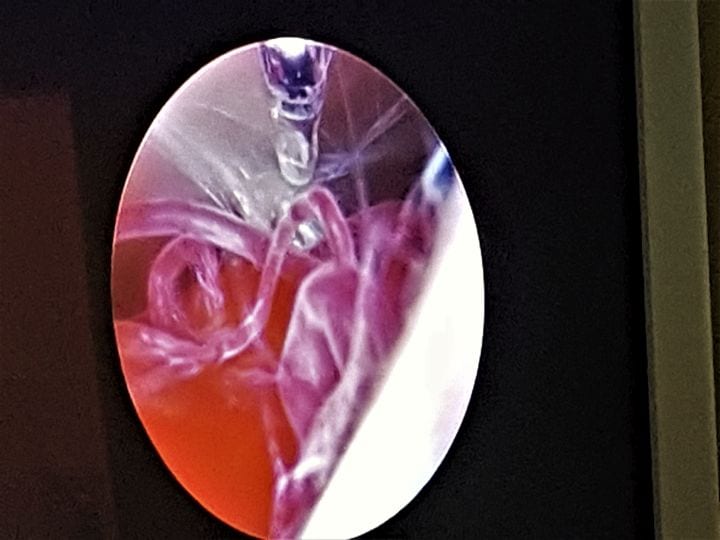

Αρχικά ο νευροχειρουργός πραγματοποιεί μικρή κρανιοανάτρηση και στη συνέχεια εισάγει προσεκτικά το νευροενδοσκόπιο, το οποίο φέρει φακό και κάμερα ώστε να μεταβιβάζει την εικόνα του εσωτερικού του εγκεφάλου μεγεθυμένη σε οθόνη υψηλής ευκρίνειας. Στη συνέχεια με τη βοήθεια ειδικών μικροεργαλείων προχωρά στην αποκατάσταση της βλάβης.